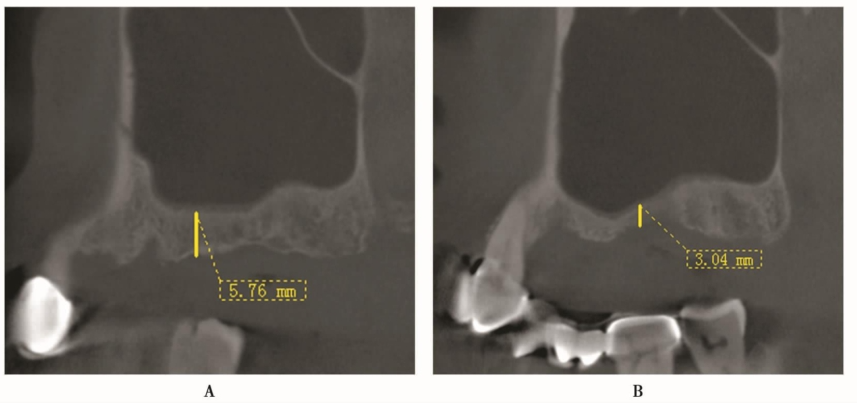

CBCT显示:患者B区牙槽骨吸收较A区严重,剩余牙槽骨高度B区约3mm(图9B),A区约6mm(图9A)。

根据CBCT的分析结果,B区选择侧壁开窗的上颌窦外提升术;为减轻术后反应,A区则选用短种植体并进行经牙槽嵴顶路径的内提升术。

图9 双侧上颌窦CBCT矢状面A.右侧A区;B.左侧B区